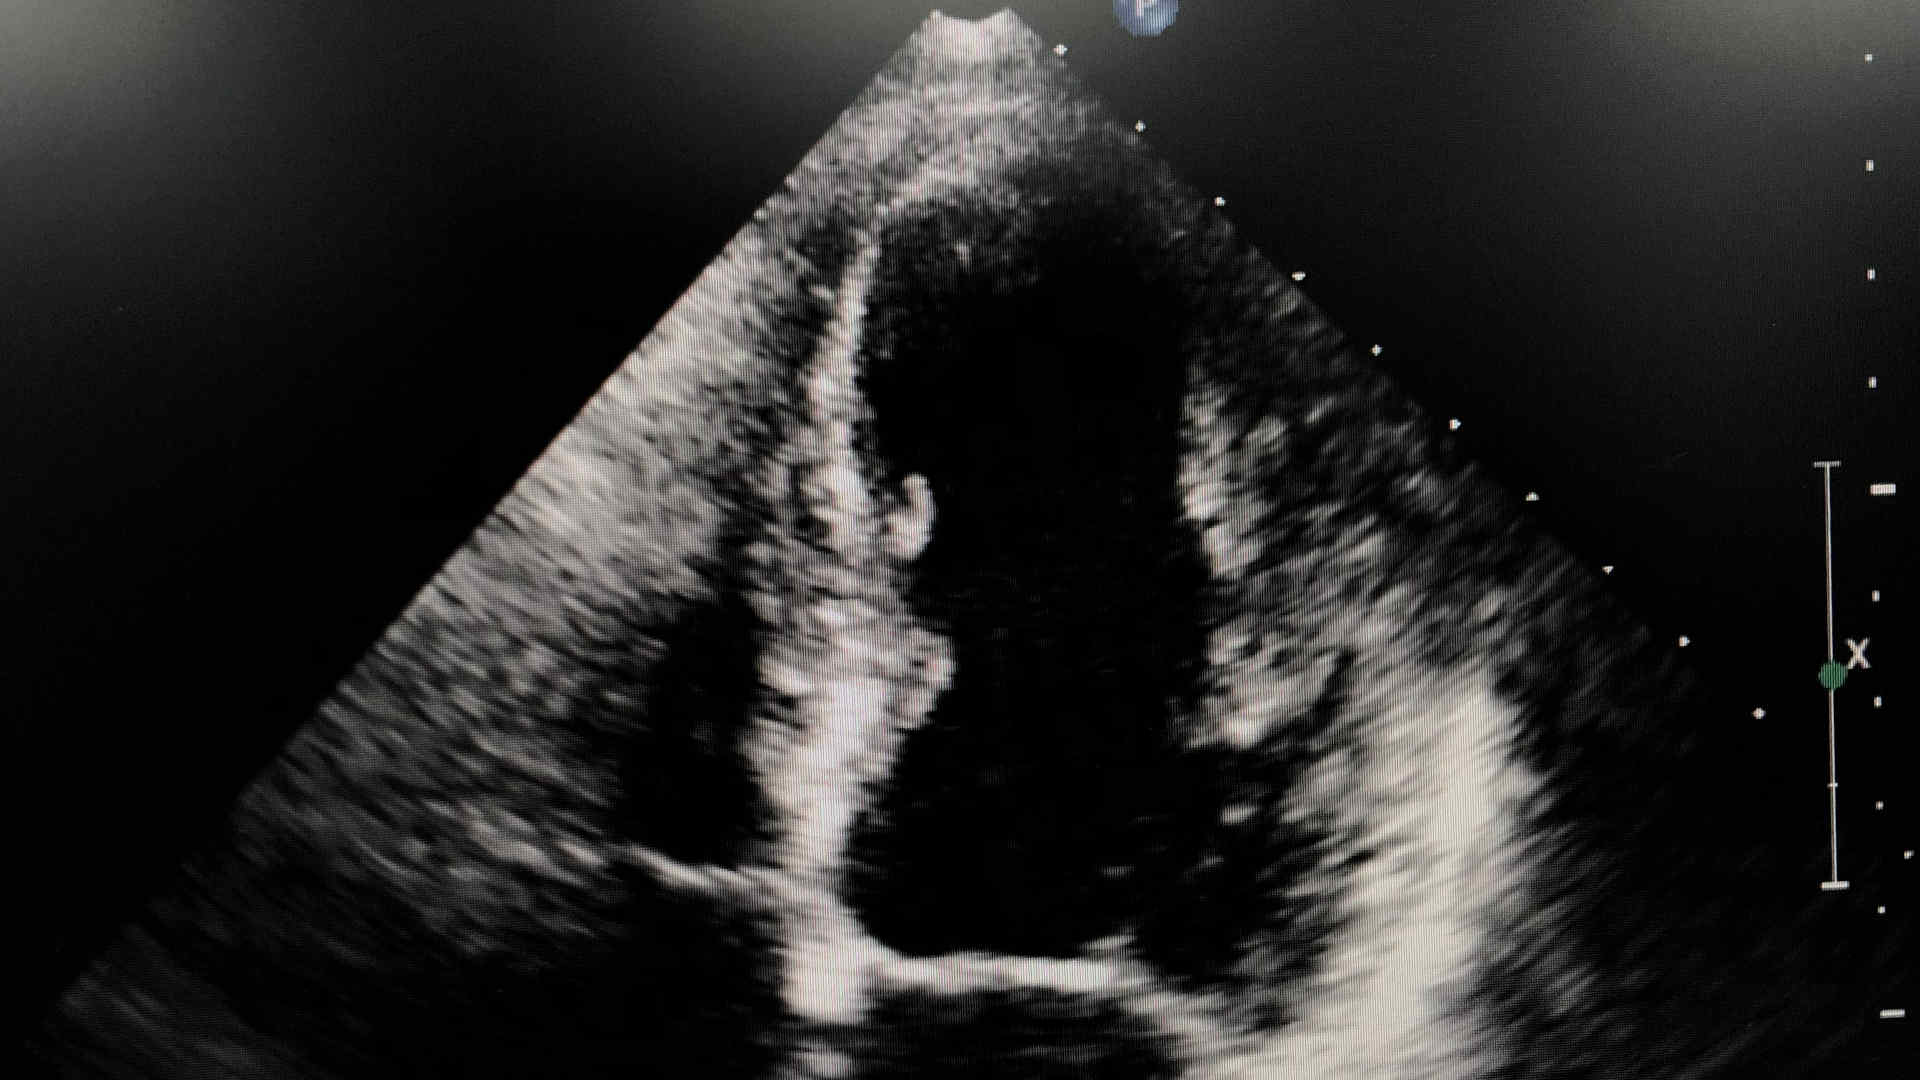

EOLIA Trial

Prof Niall Ferguson (Toronto) presents the EOLIA trial, investigating extracorporeal membrane oxygenation (ECMO) in severe acute respiratory distress syndrome